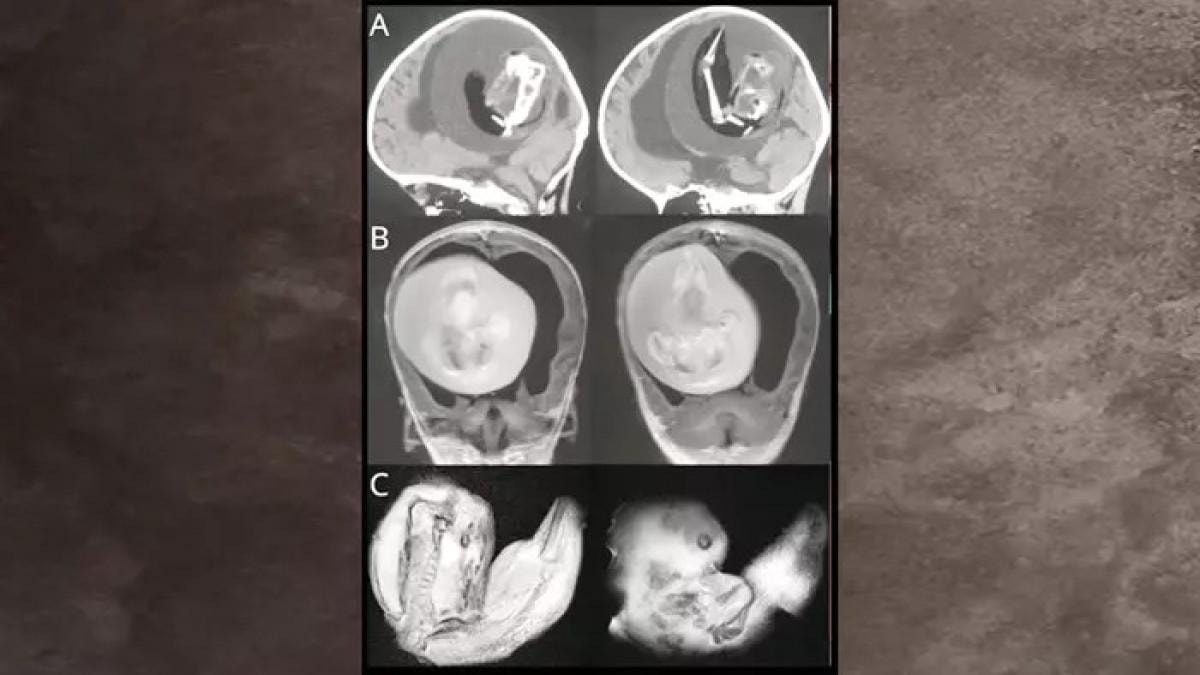

Yapılan testler, bebeğin karnında gelişimini tamamlayamayan iki hatalı fetüs bulunduğunu ortaya koydu.

Anne, 1 Şubat'ta bebeğini sağlıklı bir şekilde dünyaya getirdi. Doğumdan sonra bebeğin karnındaki gelişemeyen fetüsler cerrahi operasyonla alındı.

Taramayı yapan Dr. Prasad Agarwal, "Bebeğin karnında kemik içeren fetüs benzeri bir yapı tespit ettik. Bunun çok nadir görülen bir 'fetus in fetu' vakası olduğunu anladık" dedi.

"Fetus in fetu", tek yumurta ikizlerinde gelişim sırasında meydana gelen nadir bir anormallik olarak tanımlanıyor. Bilim insanları kesin nedenini henüz belirleyebilmiş değil. En yaygın teoriye göre, bir fetüs diğerinin içine hapsoluyor ve gelişimini sürdüremiyor.